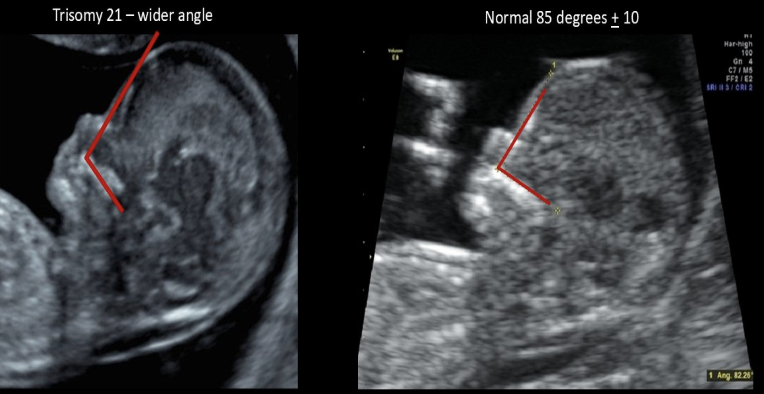

a) noonan syndrome

b) potter syndrome

c) trisomy 18

d) trisomy 21

fetal frontomaxillary facial (FMF) angle

a) is larger in normal fetuses than those w/aneuploidy

b) is measured in fetuses w/suspected trisomy 21

c) is measured after birth to see the true age of the fetus

d) should be measured on a fetus w/suspected cleft palate